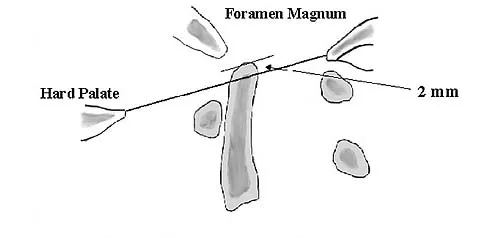

A 68-year-old woman with a history of rheumatoid arthritis has had neck pain and weakness in all four extremities that has become worse in the past 6 months. She has gone from a community to a household ambulator and uses a wheelchair outside of the home. Examination of the extremities reveals poor coordination, diffuse weakness, hyperactive reflexes, and bilateral sustained clonus. She has a broad-based and unsteady gait. The posterior atlanto-dens interval is 12 mm. Based on these findings and the radiograph and MRI scan shown in Figures 13a and 13b, the treatment of choice is surgical decompression and stabilization. However, the patient inquires about the prognosis with surgery compared to nonsurgical management. Assuming there are no complications from surgery, the patient should be informed that, with surgery, she will most likely

Explanation